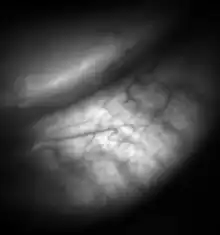

![Meibomian glands in the lower eyelid imaged under amber light to show vasculature support and the gland structure [epiCam].](../I/Meibomian-glands.png)

Dysfunctional meibomian glands often cause dry eyes, one of the more common eye conditions. They may also contribute to blepharitis. Inflammation of the meibomian glands (also known as meibomitis, meibomian gland dysfunction, or posterior blepharitis) causes the glands to be obstructed by thick, cloudy-to-yellow, more opaque and viscous-like, oily and waxy secretions, a change from the glands' normal clear secretions.[12][13] Besides leading to dry eyes, the obstructions can be degraded by bacterial lipases, resulting in the formation of free fatty acids, which irritate the eyes and sometimes cause punctate keratopathy.